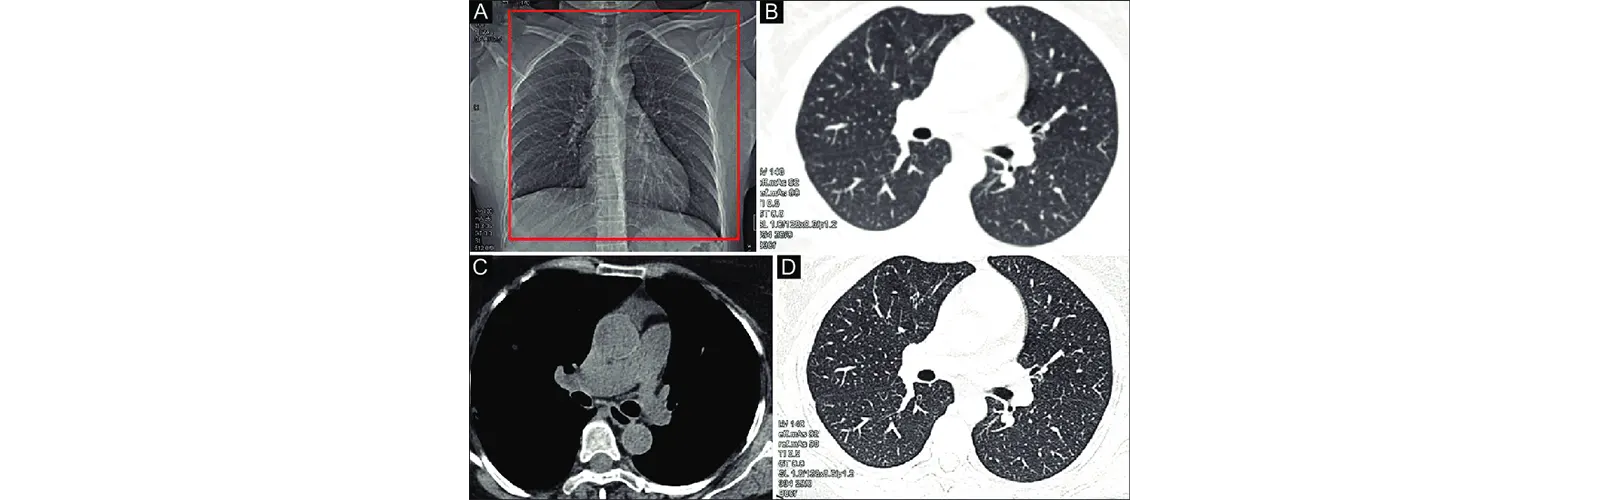

Evaluation of lung diseases: NCCT chest can provide detailed images of the lungs that can be used to evaluate various lung diseases such as chronic obstructive pulmonary disease (COPD), pneumonia, pulmonary fibrosis, and lung cancer. NCCT chest can help identify the location, size, and extent of lung abnormalities, as well as the presence of any complications such as pleural effusion or pneumothorax.

Assessment of airway abnormalities: NCCT chest can provide detailed images of the airways, which can be useful in the assessment of airway abnormalities such as bronchiectasis, bronchial stenosis, and tracheal narrowing. NCCT chest can help identify the location and extent of the airway abnormalities, which can guide treatment decisions such as the use of bronchodilators or surgery.